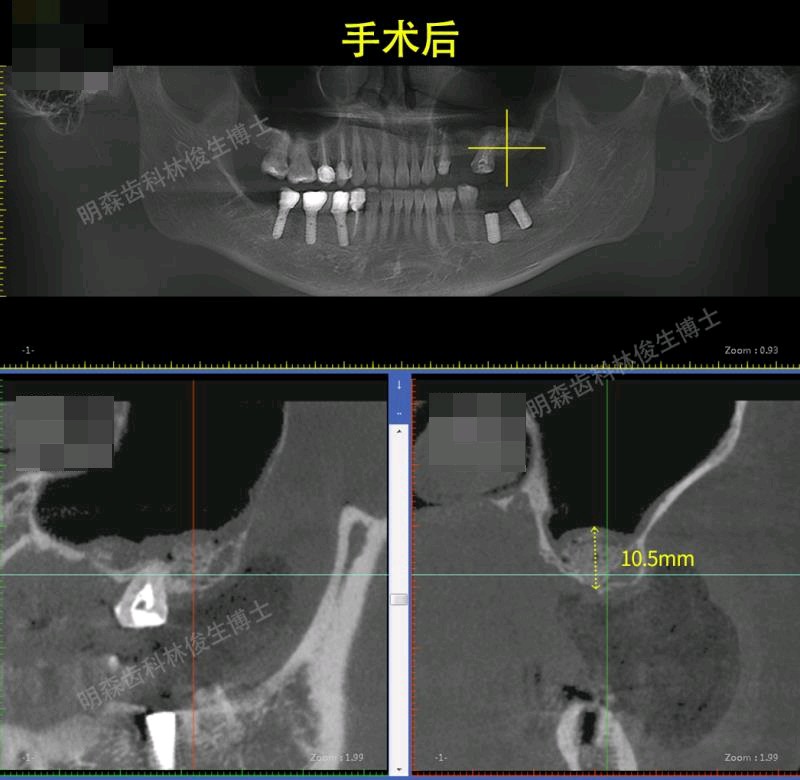

治疗方案:1.建议13-23贴面+14,15,33-43贴面修复,上前牙邻面龋补牙。 2.38.48拔除 3.24-26连冠修复,14.15换全瓷冠 4.25,27外提+植骨+种植,36,37种植修复(ITI钛锆)5.17充填治疗

此患者已跟踪近三年,一切情况良好。令我印象最深刻的是,刚种完25、27回家没多久,就微信我说没啥感觉,晚上能不能打球。。。。。看来对篮球是真的热爱啊,NBA没他,我不看。提醒大家,不管种牙后有没有不适感,都要好好休息,不要进行剧烈运动、不要熬夜,谨遵医嘱。